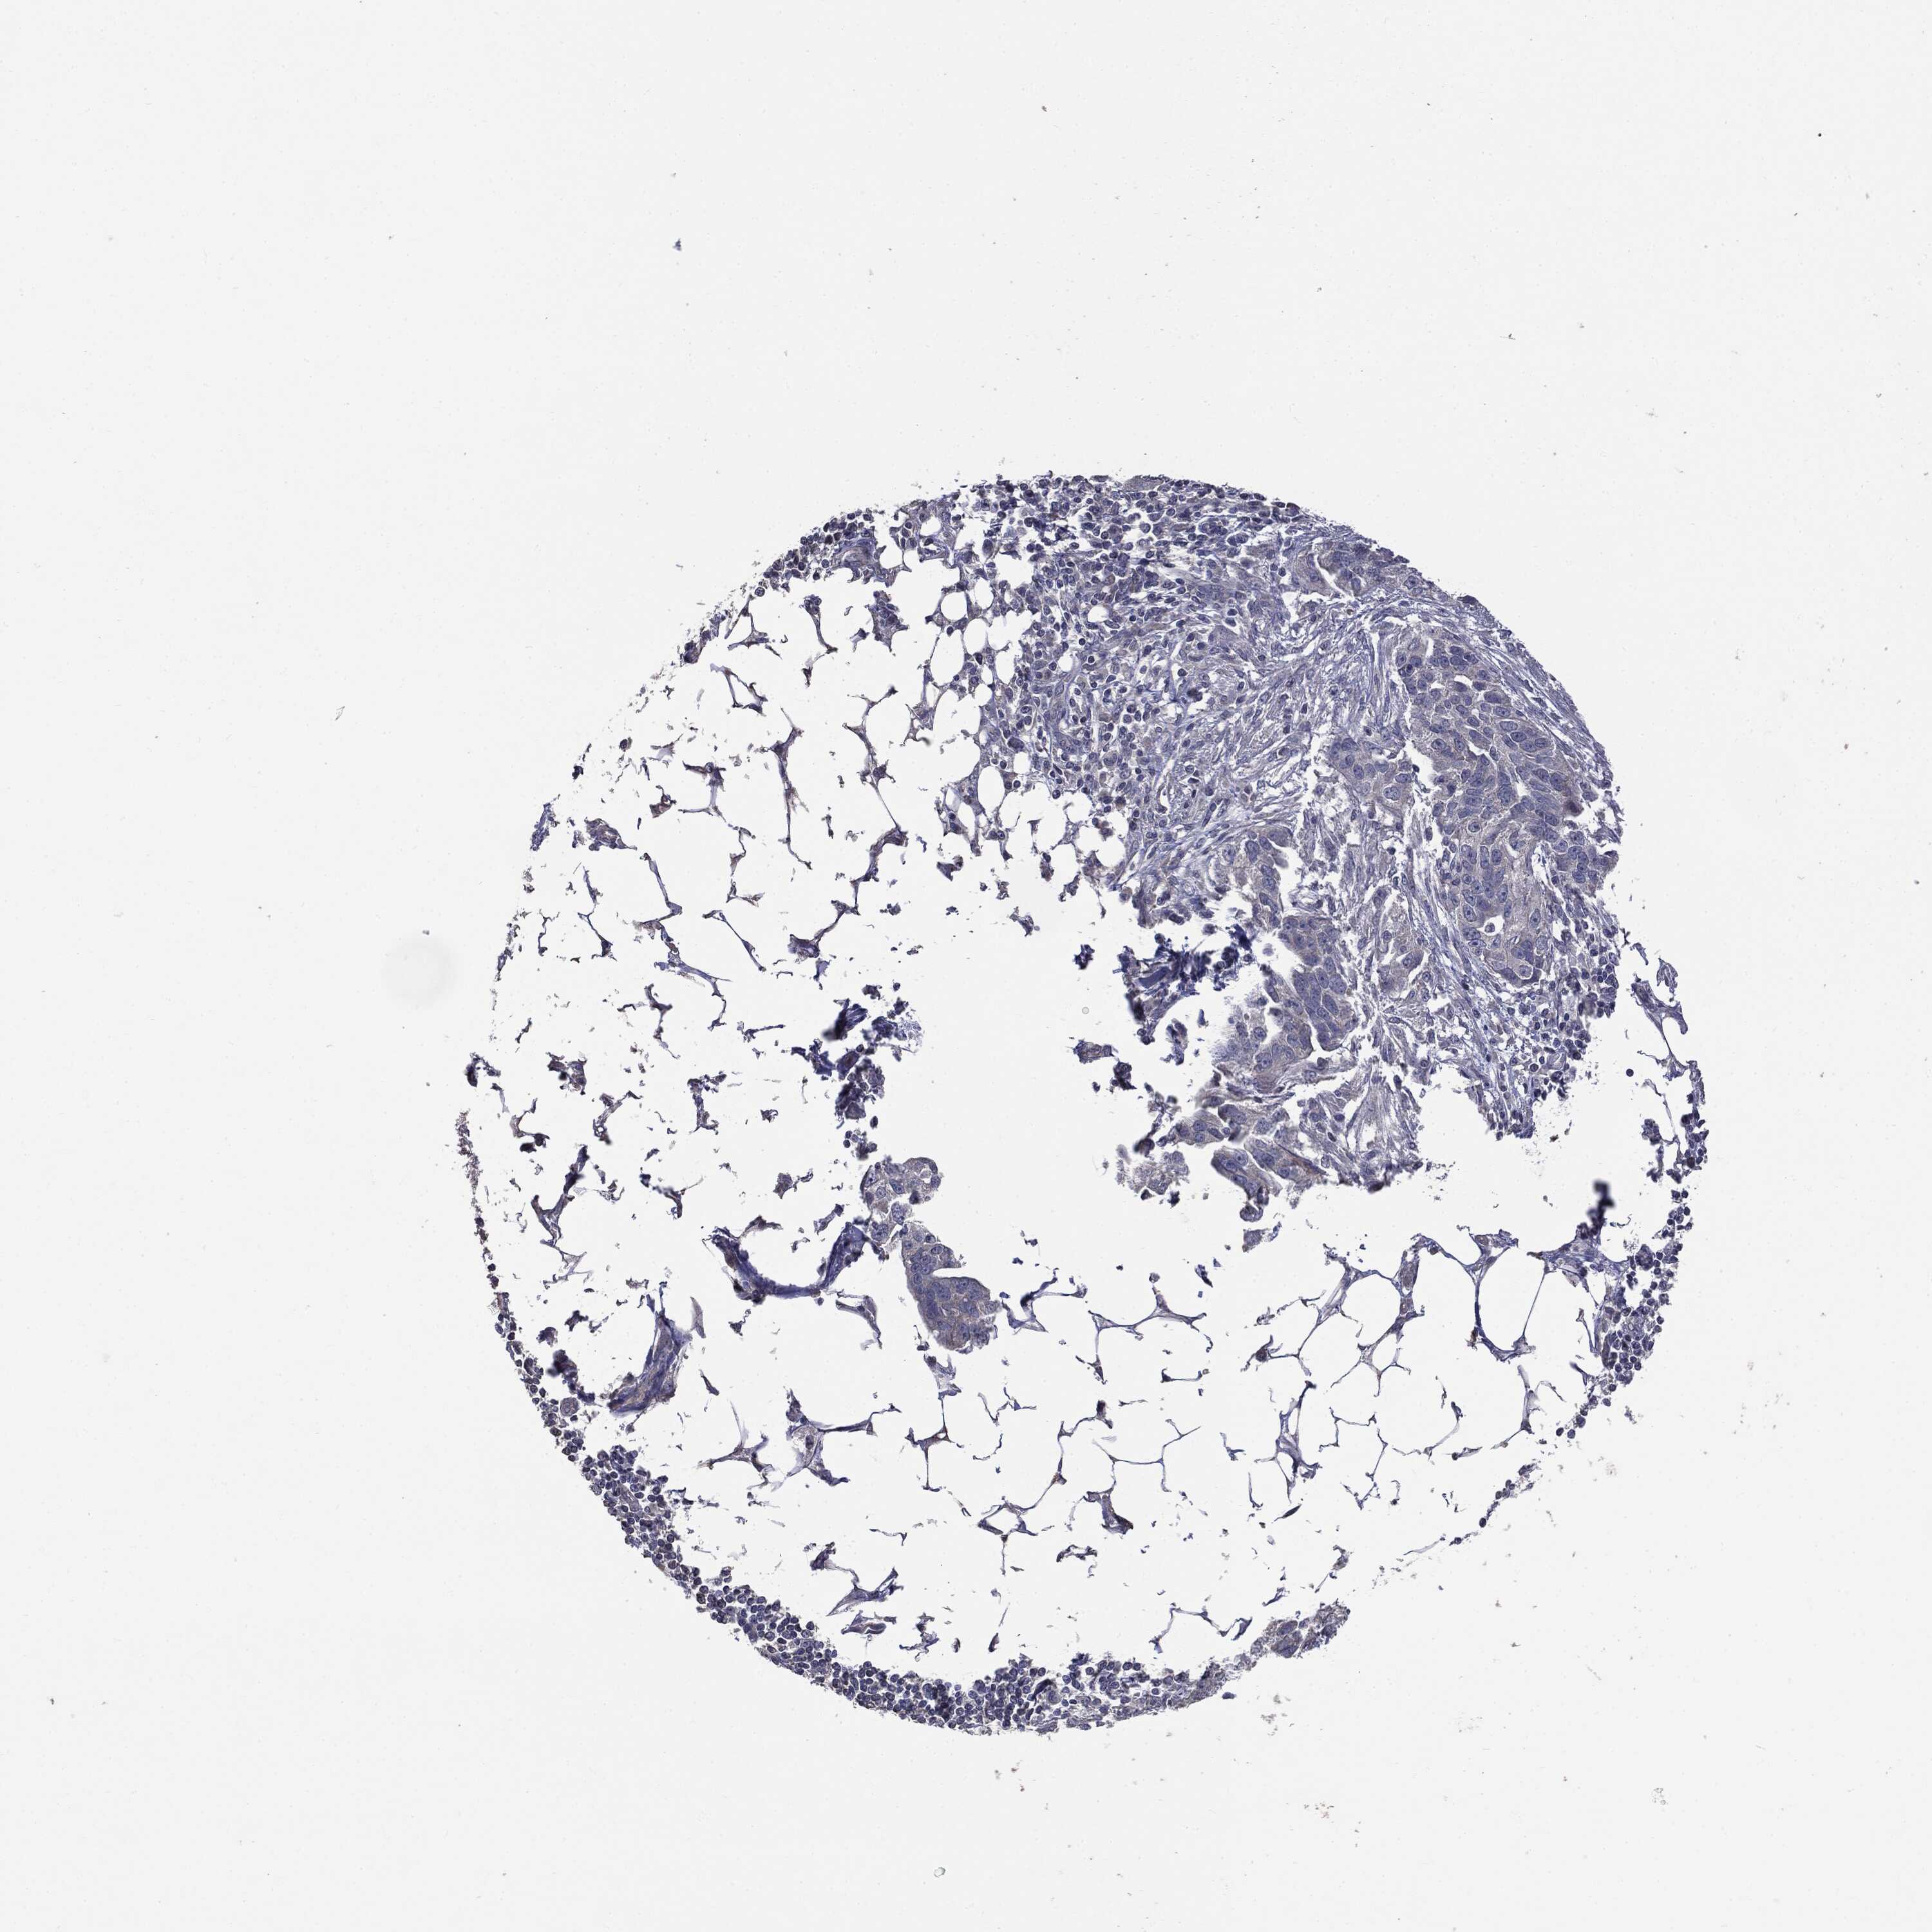

OVARIAN CANCER - Protein expressioni

A mouse-over function shows sample information and annotation data. Click on an image to view it in a full screen mode. Samples can be filtered based on level of antibody staining by selecting one or several of the following categories: high, medium, low and not detected. The assay and annotation is described here.

Note that samples used for immunohistochemistry by the Human Protein Atlas do not correspond to samples in the TCGA dataset.

Antibody stainingi

Antibody staining in the annotated cell types in the current human tissue is reported as not detected, low, medium, or high, based on conventional immunohistochemistry profiling in selected tissues. This score is based on the combination of the staining intensity and fraction of stained cells.

Each image is clickable and will lead to virtual microscopy that enables deeper exploration of all samples and also displays staining intensity scores, fraction scores and subcellular localization as well as patient and tissue information for each sample.

CAB080070

Carcinoma, endometroid